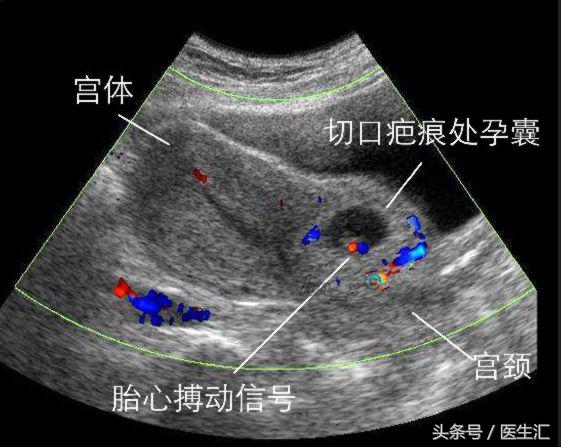

患者郝某,女,44岁,以“停经56天,发现瘢痕部位妊娠3天”之主诉入院。19年前因高血压,臀位剖宫产一活婴,此次妊娠后B超提示:子宫前壁下段剖宫产切口处见孕囊大小1.0×0.8×1.1cm,未见胚芽及心管搏动,似“三角”形,剖宫产切口下方子宫肌壁连续性尚完整,较薄处0.24cm,孕囊外缘距剖宫产切口肌层外缘0.3cm,提示切口妊娠(内生型),为求进一步治疗,来我院,门诊以“瘢痕处妊娠”。

2.超声检查是最有效和可靠的工具,早期妊娠时子宫颈管及宫腔均正常,子宫峡部前壁有包块,向前隆起,贴向膀胱,外缘距浆膜层薄,一般均小于5mm,最薄1~2mm。

B超图象中孕囊呈低回声,偶见胚芽及心管搏动,若浆膜层破裂,腹腔内有积液。彩色多普勒可见孕囊周围有丰富彩声血流信号.